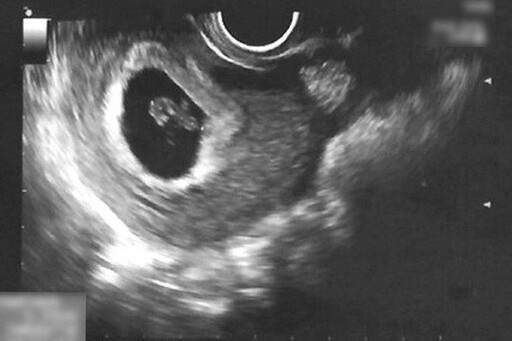

▲陳女士懷孕第六週,透過超音波檢查發現子宮腔內出現血塊(紅圈處)。

▲經過一週的中醫住院治療,子宮腔內血塊已消失,且胎兒順利成長。